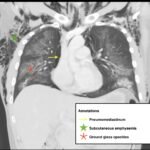

Electronic cigarette (e-cigarette) or vaping associated lung injury (EVALI) cases have increased with the popularity of e-cigarettes in the mostly young, healthy population. Some common symptoms associated with EVALI include shortness of breath and chest pain, and the most common diagnostic imaging findings are organizing pneumonia and diffuse alveolar damage seen on computed tomography (CT). Pneumomediastinum is a known sequela of EVALI.1 In the setting of pneumomediastinum in EVALI, EVALI is a diagnosis of exclusion, so other sources of pneumomediastinum need to be evaluated. EVALI has diverse presentations, and this case is a unique representation of a disease process that is becoming more commonplace with the increase in popularity of vaping. It is important to be aware of the clinical symptoms of EVALI, which can be nonspecific and can include gastrointestinal symptoms along with respiratory symptoms. It is equally important to recognize the diverse image findings of EVALI, which can include subcutaneous emphysema and pneumomediastinum. In this case, pneumomediastinum is seen in EVALI, and the patient was successfully treated with empiric antibiotic coverage, steroids, and conservative measures—making sure to limit any coughing or increases in intrathoracic pressure that can cause worsening of pneumomediastinum.

EVALI, vaping, pneumomediastinum, E-cigarette, ground-glass opacity.